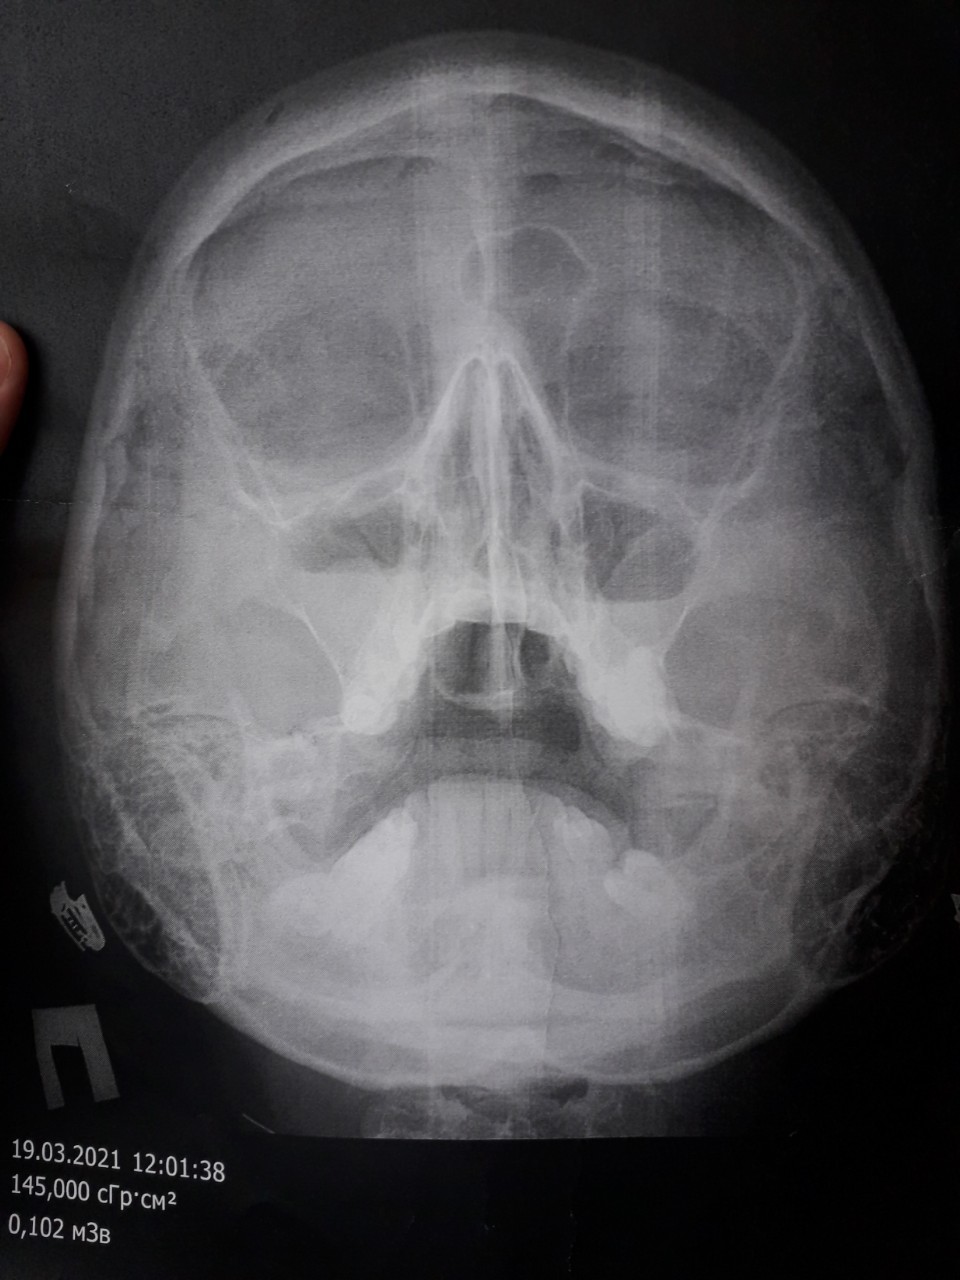

Здравствуйте, очень вас прошу помочь разобраться. У меня киста в правой гайморовой пазухе, я записалась на прием к врачу, который будет мне ее удалять, на 23 апреля. Но 3недели назад у меня стали отекать верхнии веки по утрам, могут и в течении дня отеки появится, если я прилягу. Я сходила к лору в бесплатную полеклинику, мне назначили снимок(фото 1), сказала что у меня острый гаймарит, симптомов никаких кроме насморка не было. Я пропила цетиризин, цефиксим, синупрет и назифрин капала, пришла на прием после лечения, врач снова назначила снимок, и по нему ничего не прошло. Снова назначила лечение цефтриаксон, спрей в нос мометазон, цетрин. И сказала промывать нос изотоническим р-м. Еще у меня сухой небольшой кашель, то есть то нет его. Скажите пожалуйста, могут ли быть отеки у меня из за гаймарита(потому что лор у еоторой я была, молодая девочка, уверяет что нет)? и может ли быть кашель от гаймарита? А то я накрутила себе уже все самое худшее(